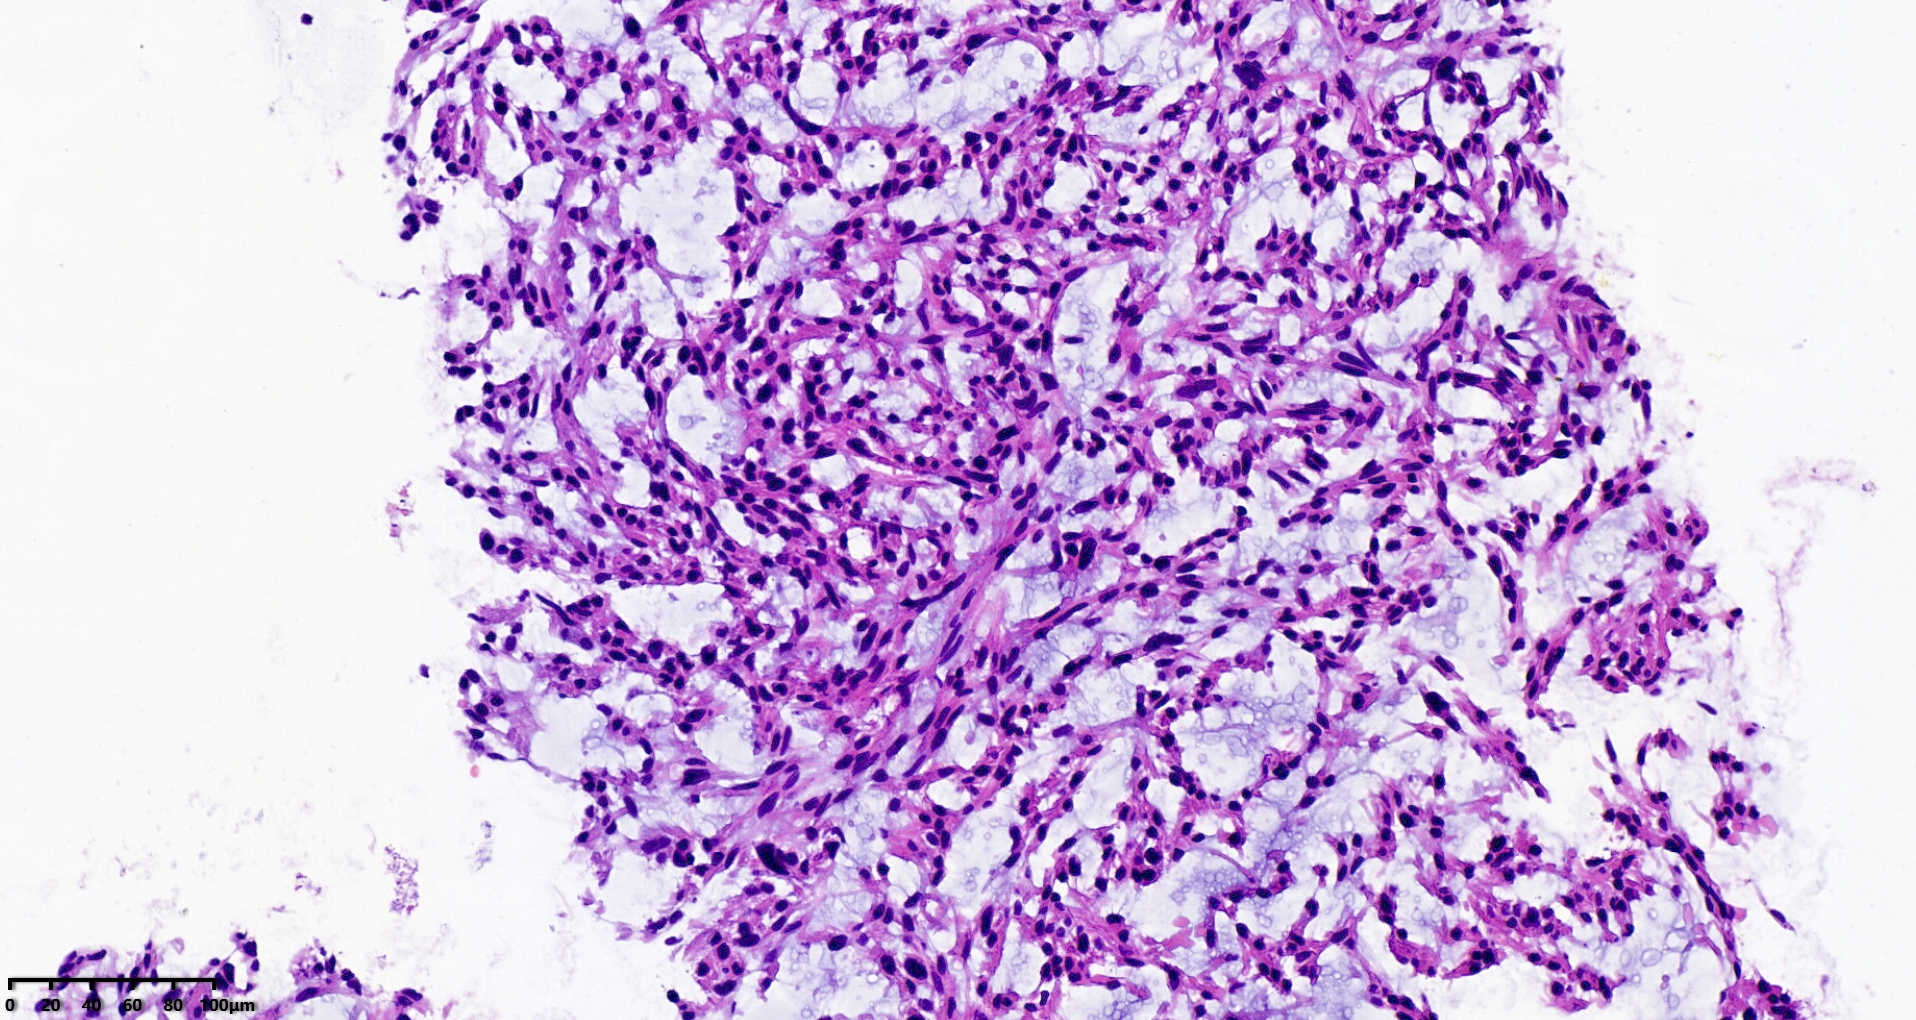

腹盆腔穿刺

腹盆腔肿物10.5×21.5cm大小

穿刺组织1.0×1.0cm

S100、CD34、MDM2、STAT6、CD117、CK均阴性

图1

考虑:深部软组织平滑肌肉瘤